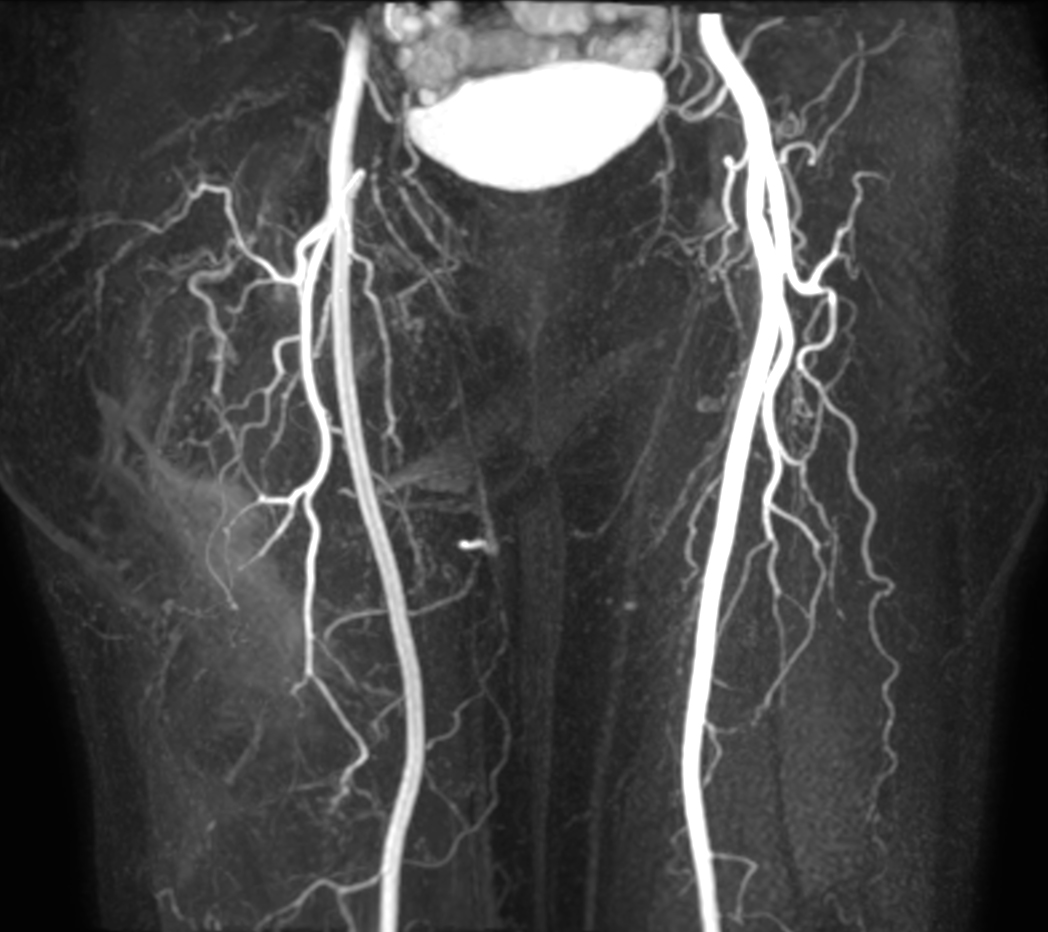

mDIXON MRA (MIP) - Abdomen